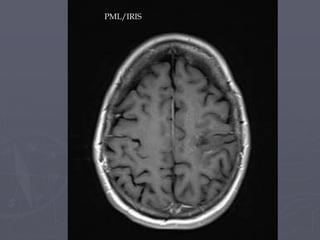

PML – profound T1 hypointensity

PML/IRIS